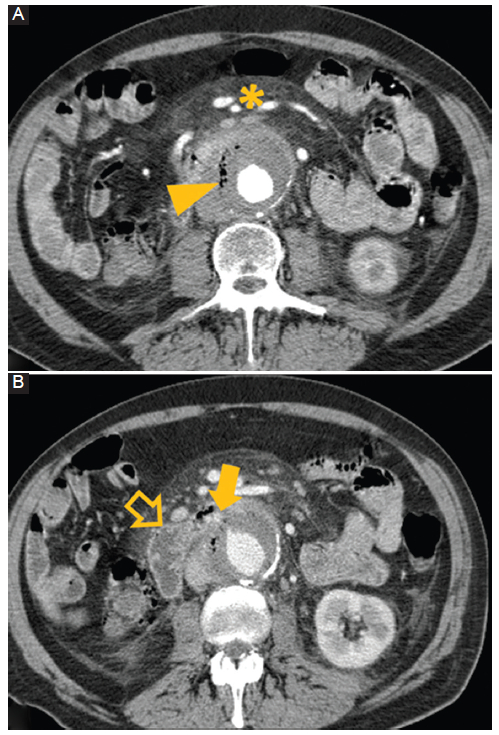

Rotura de un aneurisma: un aneurisma se define como una dilatación focal de la arteria con respecto a su tamaño original. La probabilidad de rotura en un aneurisma depende del tamaño, crecimiento en el tiempo, del antecedente de tabaquismo crónico y de la presencia de hipertensión no controlada3. Se observa discontinuidad parietal focal, hematoma retroperitoneal, extravasación activa de medio de contraste y el signo de la luna hiperatenuante (Fig. 3) (4,5.

Figura 3

Rotura de un aneurisma. Hombre de 62 años. Dolor abdominal e hipotensión. TC con contraste cortes axiales A y B: se observa un aneurisma aórtico abdominal roto (flecha) con un extenso hematoma retroperitoneal (flecha hueca) y hemorragia activa demostrada por extravasación del medio de contraste (punta de flecha).